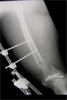

Later,treated with acute shortening and stabilsation wit Ilizarove fixator for chronic osteomyelitis

Pre

Op